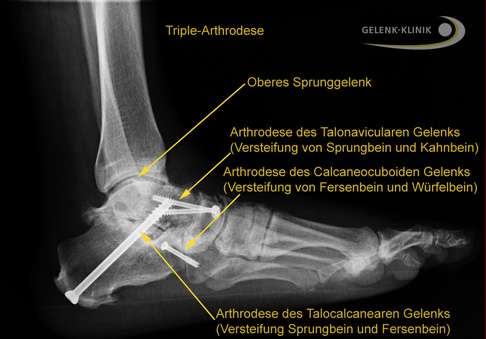

Bei einer Triple-Arthrodese werden alle drei Anteile des unteren Sprunggelenks versteift, also alle Fußgelenke, die mit dem Sprungbein verbunden sind. Dazu zählen das zwischen dem Sprungbein und dem Fersenbein liegende talocalcaneare Gelenk (TCG oder Subtalargelenk) und die beiden vor dem Sprungbein liegenden Gelenke: das Sprungbein-Kahnbein-Gelenk (talonaviculares Gelenk, TNG) und das Fersenbein-Würfelbein-Gelenk (calcaneocuboidales Gelenk, CCG), welche gemeinsam das sog. Chopart-Gelenk bilden.

Für die Triple-Arthrodese entfernt der Fußchirurg zunächst den Knorpel in den betroffenen Gelenken: im Sprungbein-Fersenbein-Gelenk, im Sprungbein-Kahnbein-Gelenk und im Fersenbein-Würfelbein-Gelenk an der Fußwurzel.

Als nächstes werden die Knochenflächen vorbereitet, damit sie optimal zusammenpassen. In einigen Fällen ist es notwendig, Teile des Knochens zu entfernen oder zu glätten. Dann fixiert der Operateur die Knochen in der gewünschten Position. Dies kann mithilfe von Schrauben, Platten, Nägeln oder Drähten erfolgen, die die Knochen stabil aneinander halten.